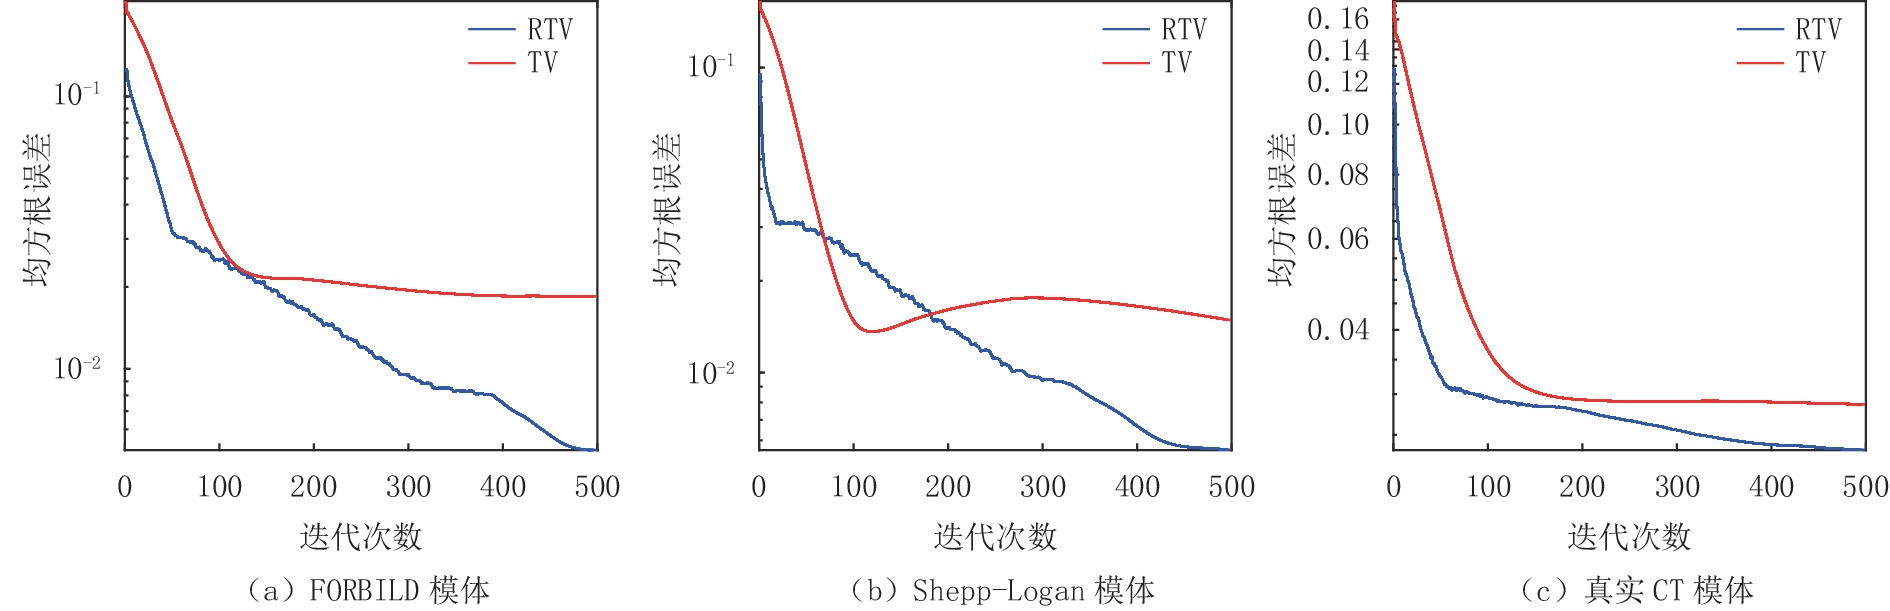

图6中的(a)图显示了FORBILD模体在20个投影角度下使用RTV和TV最小化重建算法的RMSE趋势曲线的比较,显然,RTV最小化重建算法经过500次迭代达到收敛点后拥有更高的重建精度,其最终的收敛精度是30×10-5。而TV算法最终的收敛精度只有5130×10-5。

图6中的(b)图显示了Shepp-Logan模体在20个投影角度下使用RTV和TV最小化重建算法的RMSE趋势曲线的比较,显然,RTV最小化重建算法经过500次迭代达到收敛点后拥有更高的重建精度,其最终的收敛精度是8.010×10-5。而TV算法最终的收敛精度只有1610×10-5。

图6中的图(c)显示了真实CT模体图像在20个投影角度下使用RTV和TV最小化重建算法的RMSE趋势曲线的比较,显然,RTV最小化重建算法经过500次迭代达到收敛点后拥有更高的重建精度,其最终的收敛精度是0.0403。而TV算法最终的收敛精度只有0.0467。

图11显示了FORBILD、Shepp-Logan和真实CT模体图像在50个投影角度,并于投影数据中加入方差为0.05的高斯白噪声条件下分别使用RTV和TV最小化重建算法进行重建的RMSE趋势曲线的比较,从表4~表6中的数据可见这两种算法在3个模体上的重建精度分别为0.005和0.01842、0.0055和0.0148、0.0233和0.0286,从定量分析来看显然RTV最小化算法抑制噪声,保护图像结构的效果更好一点。